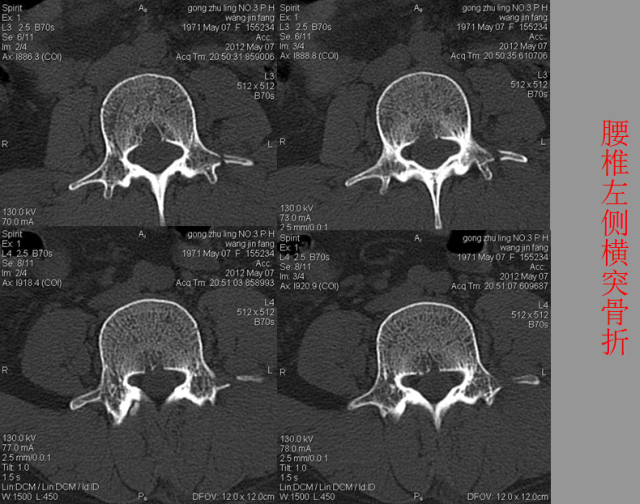

骨折篇

01

定义:骨折{Fracture}是指骨的完整性和连续性的折裂或粉碎。包括创伤性骨折、疲劳性骨折和病例理性骨折。 临床上以创伤性骨折*常见。